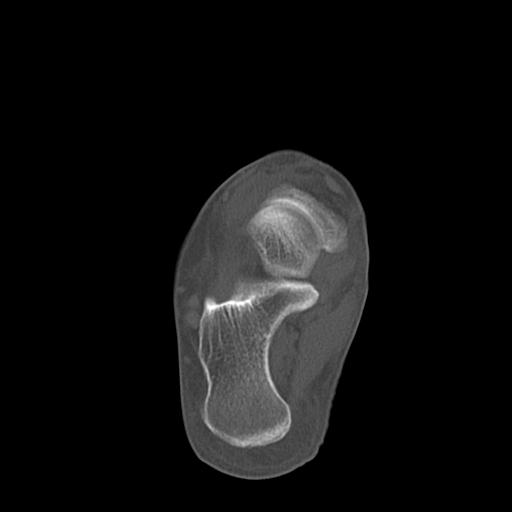

102755 1/4 2R 1/15 2R 右足関節 68歳女性 右三果脱臼骨折